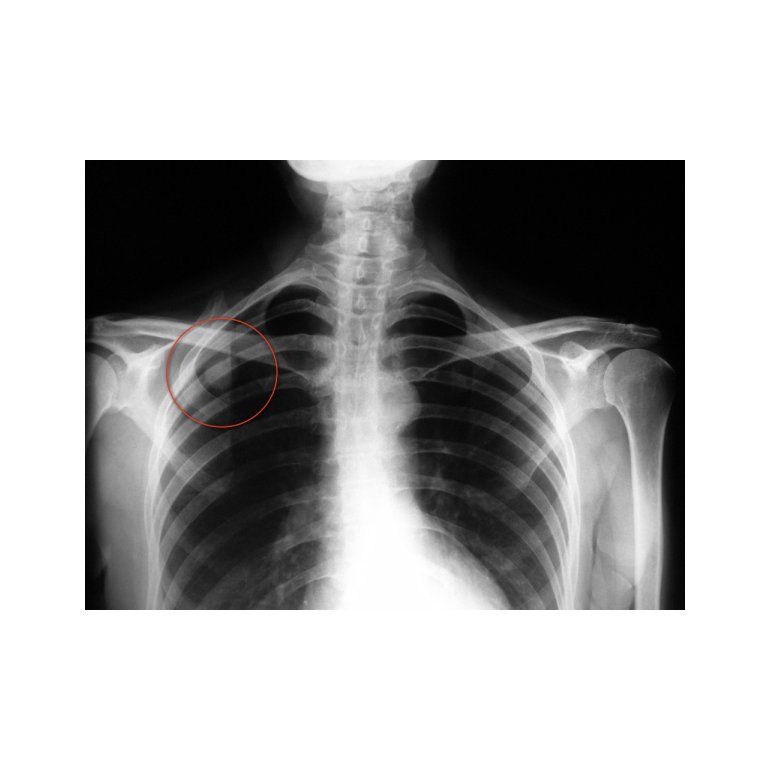

Pero, ¿qué es un nódulo pulmonar?

Si bien son asintomáticos, pueden aparecer en un screening o en una radiografía de tórax. Y si el médico tiene alguna sospecha, se puede confirmar con otros estudios, como por ejemplo una tomografía computada. De todas maneras, se hace un seguimiento más focalizado para ver cómo se va comportando con el fin de observar si sufre modificaciones de tamaño, de forma o de característica.